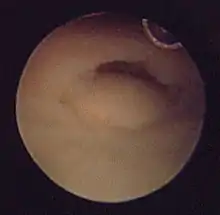

An arthroscope can be used at the time of fixation to evaluate for soft-tissue injury and the congruity of the joint surface and may increase the accuracy of joint surface alignment[19] Structures at risk include the triangular fibrocartilage complex and the scapholunate ligament. Scapholunate injuries in radial styloid fractures where the fracture line exits distally at the scapholunate interval should be considered. TFCC injuries causing obvious DRUJ instability can be addressed at the time of fixation.